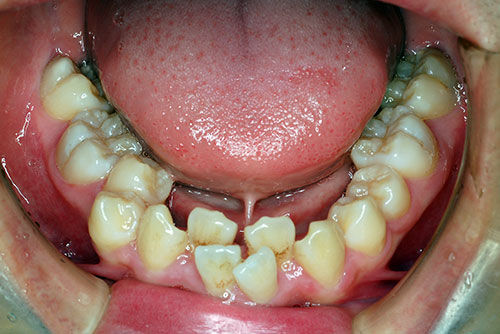

下の写真は舌小帯が短いため(舌小帯拘縮症)に、下顎歯列の成長が十分でなかったため下顎前歯が二枚歯状態になった叢生症例です。なお、舌小帯拘縮症も学校歯科健診の診査項目に入っております。舌の小帯(ヒモ)を伸ばす手術は、簡単な手術で治すことができ、健康保険が適用されます。浜松市であれば18歳までなら費用は500円で済みます。出来ればリハビリテーションとして専門医あるいは言語聴覚士(ST)を受診して、舌のトレーニングを受けるのが望ましいと考えます。